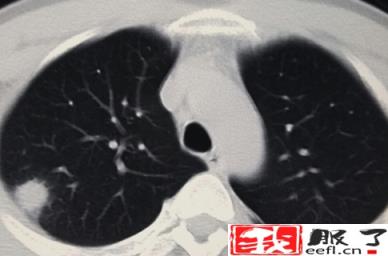

正常人群肺结节检出率因地区而异。根据目前的情况,最低可能是20%,最高可能是40%-50%,甚至70%,这可能与参与调查的正常人群有所不同。年龄不一样。 30-70岁的正常人可能会发现70%的人有肺结节,一般在20%-40%左右。肺结节发生率高,但恶性程度低。有可能90%以上的肺结节是良性结节,最终诊断为恶性肿瘤的约有5%左右。

肺结节的发病率虽然高,但主要是由非肿瘤因素引起的。由于肺癌是最常见的癌症,大家对肺癌的关注度也越来越高。肺癌的监测和筛查方法通常是胸部CT。胸部CT做的越多,肺结节的发生率和检出率就会增加。由于肺癌仅占其中的5%左右,因此肺结节大可不必过于紧张。 .必要的检查、观察和随访更为重要。做到早筛查、早发现、早治疗。大多数肺癌患者都能取得较好的治疗效果。